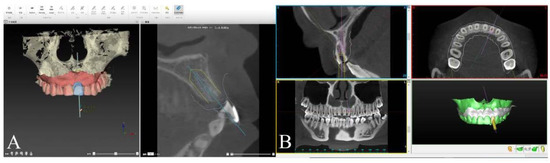

2.3. Implant Planning Procedure and Template Fabrication